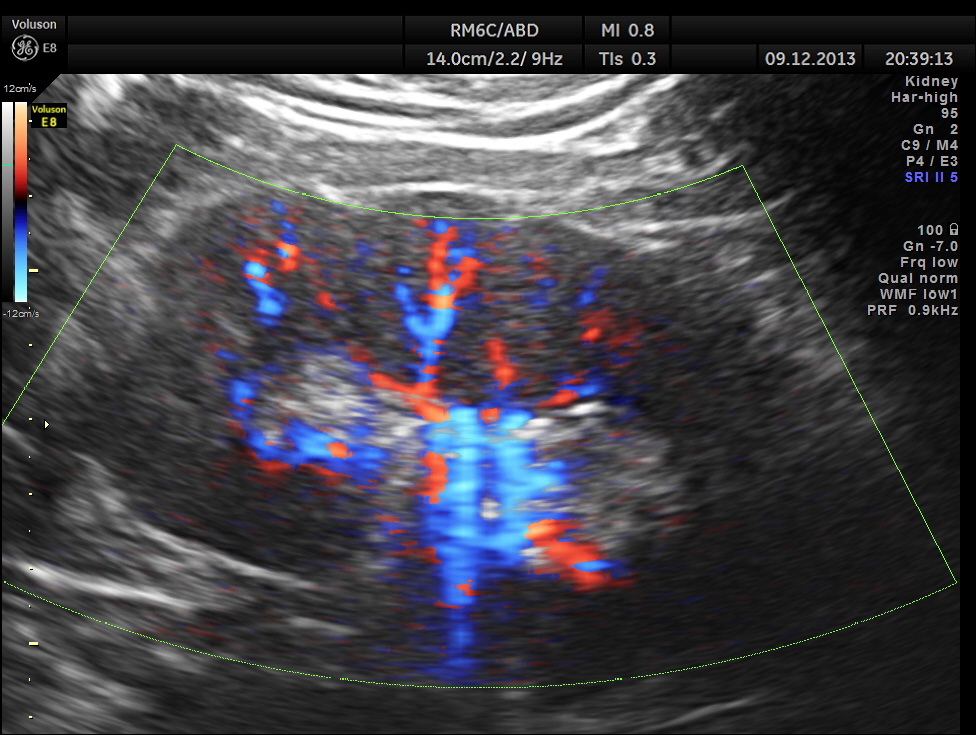

Power Doppler of the right kidney.

Regular power doppler appears unremarkable.